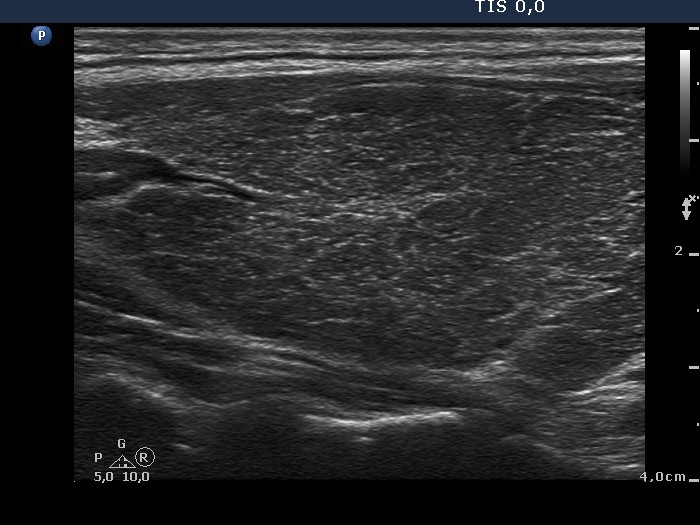

Ultrasonography. A diffusely hypoechogenic thyroid was found with extensive fibrosis. There was an echonormal nodule in the upper dorsal part of the left lobe. The nodule showed taller-than-wide shape and halo sign while the presence of perinodular blood flow was equivocal.

1. The extensive fibrotic change is a not rare situation in the case of Graves' disease. We can demonstrate the possible misinterpretation of granular presentation of fibrosis - see comment to ultrasonographic picture.

2. Malignancy occurs only exceptionally in an echonormal nodule except for autoimmune thyroid disorders. We must be aware that the echo structure of a nodule may be influenced by the echo structure of the non-nodular thyroid. Therefore, echonormal nodules are targets of cytological investigation in hypoechogenic thyroids, i.e. Graves' disease and in Hashimoto's thyroiditis.

3. The presence of perinodular blood flow is doubtful because the nodule is avascular while the vascularization of the extranodular part is extremely increased. Nevertheless, the nodule proved to be encapsulated on histopathology.

6. The histogram value of the nodule proved to be 74.8, a value which is less than the average of the normal parenchyma, therefore in absolute sense, this is a minimally hypoechoic nodule. In relative sense, compared to the non-nodular part of the particular case, the nodule is hyperechoic.